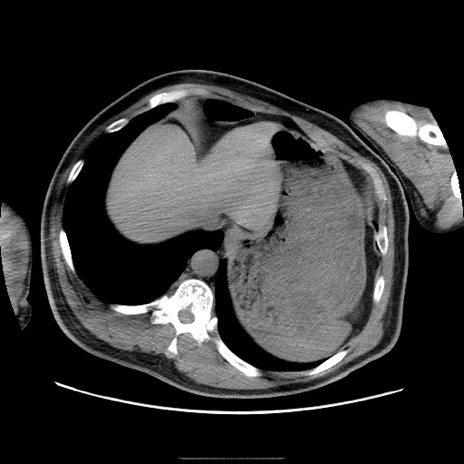

症例22(横断像)

【症例】50歳代男性

【主訴】腹痛

【現病歴】AVMからの被殻出血のため回復期リハ病棟入院中。 本日午後3時頃急に下腹部痛が出現した。

【既往歴】AVM、被殻出血、虫垂炎、高血圧

【身体所見】意識晴明、左半身不全麻痺、会話の理解は良好、36.5°C、腹部:膨隆、全体に板状硬、下腹部正中に圧痛点あり、反跳痛-、筋性防御不明、右下腹部にope scar

【データ】WBC 9400、CRP 0.06